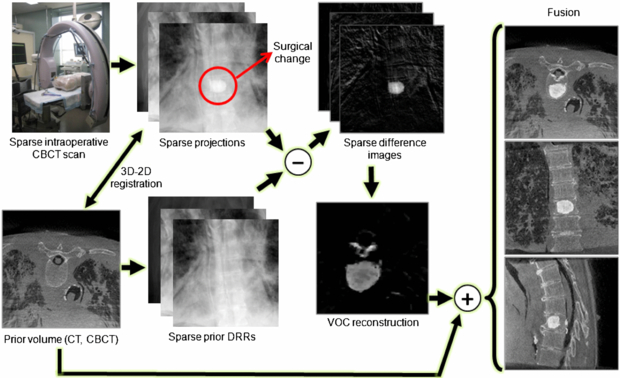

This paper proposes a new strategy to achieve both high-quality and low-dose intraoperative imaging. This is possible by extensively utilizing prior knowledge of the patient anatomy, which can reduce reliance on fluoroscopy, augment full 3D acquisitions, and complement the overall intraoperative imaging and navigation system. We propose to reconstruct the region of surgical change accurately by integrating patient-specific prior information into intraoperative C-arm CBCT for low-dose, high-quality 3D imaging in image-guided surgeries. The proposed approach involves patient-specific prior information such as preoperative CT or CBCT, sparse intraoperative CBCT scan, 3D–2D registration between the prior volume and the intraoperative scans, difference image computation, and VOC reconstruction from the sparse set of difference images followed by a fusion of the reconstructed VOC with the prior volume. A sparse scan is realized by taking larger angular steps between each projection image over the scan arc, for example, 15 projections uniformly spread over a 180° + fan angle. A sparse scan offers a means to reduce radiation dose by reducing the number of projections. An alternative means of dose reduction is to keep the number of projections constant while instead reducing the mAs per projection. The sparse-scan scenario offers the advantage of a smaller projection dataset, thereby reducing computational load in iterative reconstruction methods as considered below, but introduces a challenge of view aliasing from low angular sampling. The low mAs scenario provides reduced view aliasing but entails a large projection dataset (i.e. larger computational load) and is ultimately limited in dose reduction capability by the electronic noise of the detector. The sparse-scan scenario considered in the experiments reported below is well suited to fast, low-dose image updates in image-guided interventions. When the size of the surgical change is small, the changed region can be localized from the surgical plan and the VOC reconstruction may involve only a small volume of interest (VOI), allowing less computation than is needed to reconstruct the entire surgical field. (Note that we achieve dose reduction by using the sparse-scan approach, not by taking advantage of the small size of the VOC that is reconstructed. The latter approach is further discussed in section 9.2.) Figure 1 shows the VOC reconstruction workflow. The proposed VOC reconstruction approach was tested in a series of physical experiments, including a simulated sacroplasty with a dry cadaveric bone and vertebroplasty in a cadaveric torso. The visually promising reconstruction results were quantitatively evaluated using metrics of accuracy and perceptual difference from images acquired from a full projection dataset.

Figure 1. VOC reconstruction workflow. The surgical change illustrated is an injection of bone cement in a thoracic vertebra.

Standard image2. Incorporation of patient-specific knowledge in 3D reconstruction

Since for many surgical scenarios, the changes imparted to the patient in any given step of the procedure may be local and relatively small, there is a significant amount of redundant information, i.e. unchanged patient anatomy, between repeated scans. This implies that, if we know how to relate the already-known information to new information in the current scan, we can highlight the regional changes and restore them from a much smaller amount of data than is needed to reconstruct an entirely new image volume, which leads us to extensively utilize available patient-specific prior knowledge for intraoperative 3D reconstructions. In this paper, we use a preoperative CT or CBCT scan as patient-specific prior knowledge to augment sparse-scan data obtained during surgery. In particular, the prior anatomical model is used to generate difference projection images, ideally, showing surgical changes only, thus connecting patient-specific prior knowledge to high-quality VOC reconstructions. Specifically, instead of performing a complete CBCT scan that involves a full radiation dose, the VOC approach attempts to reconstruct only the aspects of the region that have changed since the previous scan from a sparse set of projections. Only new information, i.e. the VOC, is reconstructed, and the result may be fused with the prior volume, to present a complete and up-to-date view of the surgical field.